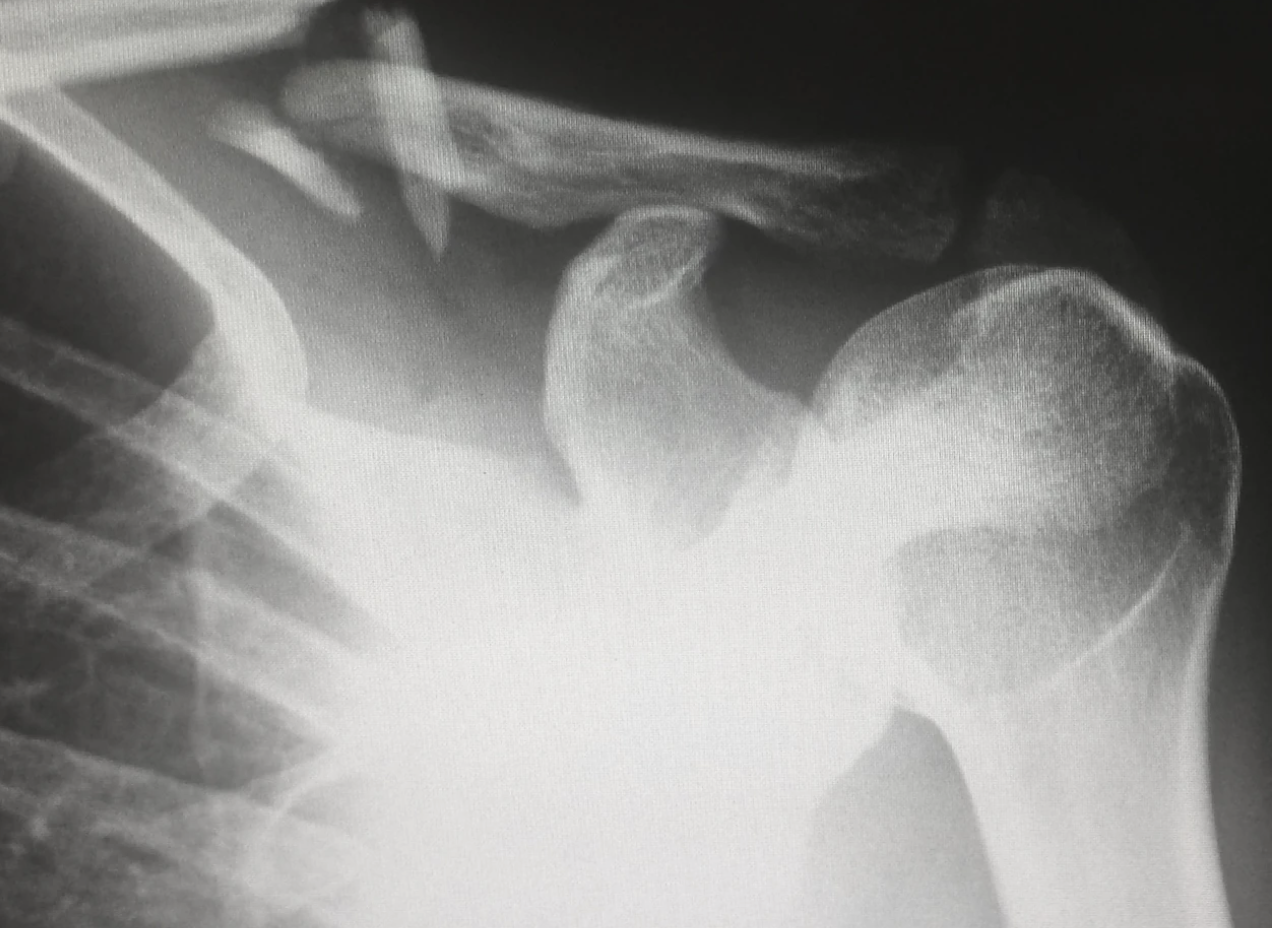

석회화 건염 어꺠 사진. 왜 석회화 건염 환자에게 운동이 중요한가?

석회화 건염은 관절 주변의 인대, 힘줄, 근육 등의 연골과 뼈가 변성되어 염증이 생기는 질환입니다. 이러한 질환은 일상생활에서 운동 부족, 자세의 부적절, 연령 등이 원인이 될 수 있습니다. 따라서, 석회화 건염 환자는 적절한 운동을 통해 건강한 관절을 유지하고 통증을 완화시킬 수 있습니다. 그러나 운동 선택이 중요한데, 너무 과도한 운동은 관절에 무리를 줄 수 있습니다. 따라서, 체력과 건강상태를 고려하여 적절한 운동을 선택해야 합니다. 이번 주제에서는 석회화 건염에 좋은 운동 5가지에 대해 알아보도록 하겠습니다.

석회화 건염은 뼈와 관절의 난치성 질환 중 하나로, 뼈와 연골 조직이 부분적으로 또는 전체적으로 석회화되는 증상을 보입니다. 이로 인해 관절 가동 범위가 제한되며, 심한 경우는 통증과 염증 등의 증상을 유발하기도 합니다. 그러나 석회화 건염 환자들이 적절한 운동을 하면, 근력 강화와 유연성 향상 등의 효과를 얻을 수 있습니다. 또한, 적당한 부하 하에서 운동을 하면 뼈의 밀도를 높일 수 있어 뼈 건강에도 도움이 됩니다. 하지만, 운동을 선택할 때에는 환자 개인의 건강 상태와 신체적 특성을 고려해야 합니다. 석회화 건염 환자들은 과도한 운동을 할 경우 부상 위험이 있으며, 급격한 움직임이나 충격이 있는 운동은 피해야 합니다. 따라서 석회화 건염 환자들은 교육받은 전문가와 상담하며, 적절한 운동 프로그램을 수행해야 합니다. 이를 통해 건강한 운동 습관을 유지하면서, 뼈 건강과 관절 기능을 개선할 수 있습니다.